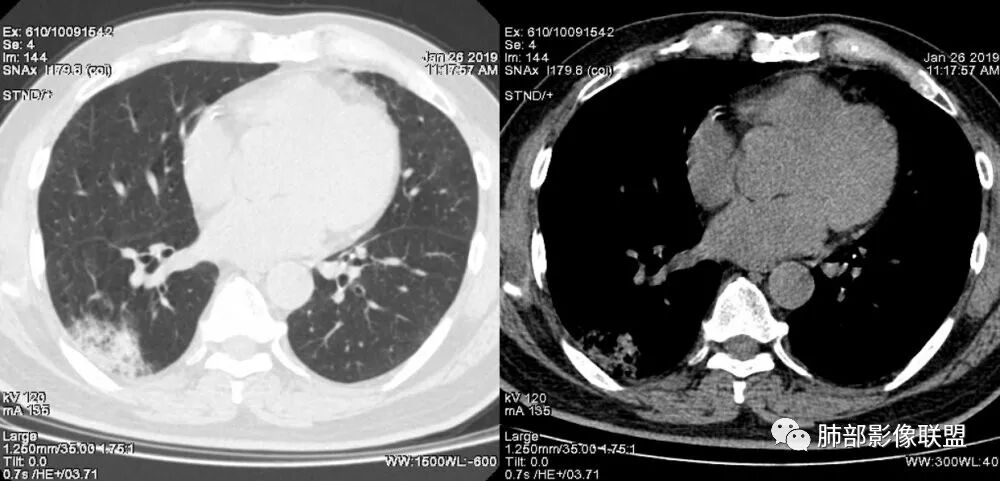

老年女性,咳嗽咳痰病史,右肺下叶大片磨玻璃实变影,胸膜下分布,支气管进入后扩张、僵直,磨玻璃影边界清楚,考虑粘液腺癌。鉴别肺炎。

老年人,右肺下叶斑片状阴影,病灶有膨胀性,边缘可见磨玻璃影,其边界清晰,内见僵硬的支气管,部分支气管扩张,首先考虑占位性病变,粘液性腺癌可能。鉴别感染性病变,后者边缘多有收缩性改变或者平直,内部支气管走形自然。

中年女性,右肺下叶沿胸膜下大片状高密度影,实变加GGO,外朝内发展,边界较清,内可见蜂窝征及枯树征,考虑肺炎型肺癌。

患者中年女性,咳嗽咳痰就诊。胸部CT:右肺下叶后基底段片状实变影,由胸膜向内发展呈扇形,病灶里有小叶内间质增厚、蜂窝状影,周围边界清楚GGO,内可见扩张支气管,淋巴结无明显肿大。综合符合粘液腺癌。

老年女性;右下肺混合实变影,呈楔形改变,边缘清晰,支气管进入且扩张,蜂窝状改变,考虑粘膜相关淋巴瘤,鉴别粘液腺癌,肺栓塞。

女,55咳嗽咳痰,右肺下叶片状实变,磨玻璃影及蜂窝影,考虑粘液腺癌。

老年女性,右肺下叶大片实变,小叶间隔及小叶内间隔增厚,边界较清,其内支气管似乎可见稍扭曲,分支减少。考虑1.肺炎型肺癌2.结合临床除外类脂性肺炎。

起源于胸膜下,实性成分,边缘Ggo,边界清晰,内可见小叶间隔增厚,粘液腺癌可能。建议先消炎后复查。

右肺下叶胸膜下大片状MGGO,其内结构紊乱,可见空泡征,病灶内近端支气管扩张,远端闭塞,形态不规则,边界部分清楚,部分似清非清,考虑粘液腺癌,鉴别淋巴瘤

该病灶主病灶位于胸膜下(肋膈角处),边缘膨隆改变,周围毛玻璃,边界清楚,病灶内支气管僵直,轻度扩张,小分支无,符合枯树枝改变,有多发小空泡(难与支气管区别),应该符合肺炎性肺癌,但无蜂窝,没有增强无法判断有无粘液、血管特点,如果周围显示的空泡是支气管,其已达到远端,这些有符合炎性特点,工作中,我会先抗炎膨后复查再定。

这是潘老师说的外向内吗?右下实变,蜂窝,GGO,支气管变形迂曲,局部膨胀感,肺炎性肺癌,粘液腺癌可能。常规先抗炎再复查。鉴别淋巴瘤,淋巴瘤支气管一般不变形,壁光整,病程长。

1.本例病灶较大片混杂密度影,胸膜下分布为主(未沿着支气管分布),该分布特点可见于大叶性肺炎、干酪性肺炎、淋巴瘤及粘液腺癌等。可惜未提供增强扫描图像。

2.病灶示中央实变区,周围GGO,可见明显小叶间隔增厚,GGO边界清楚,应当考虑到恶性病变的可能性。肺炎因炎性水肿及渗出,影像上边界常模糊不清,注意早期粘液腺癌可出现似清非清的边界。粘液腺癌因粘液成份较多,密度一般偏低,纵隔窗病灶常会消隐或范围会明显缩小,这不同于炎性实变。

3.病灶内支气管走形略显僵直,侧支少(粘液阻塞),也符合肺腺癌的枯树枝征。而大叶性肺炎的支气管是管壁光整、通畅、自然,结核的支气管常常壁增厚,甚至狭窄后扩张;

4.患者临床症状不重,临床炎性指标不高,结合肺内影像,应警惕肺炎型肺癌。